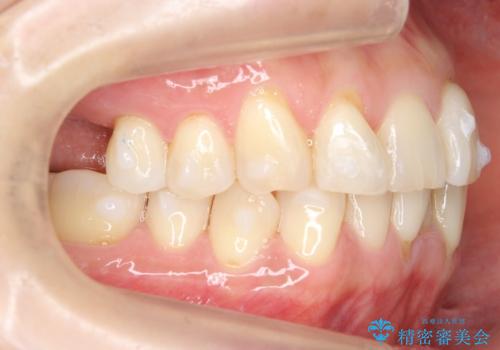

前歯が反対になっている マウスピース矯正+奥歯ブリッジ

- 前歯のがたつきを主訴に来院。

奥歯も少なく、左上奥歯はブリッジにすることになりました。

左下の前歯を中に入れるスペースを確保する目的で左下の奥歯を後ろ移動させました。

また、左下の小臼歯の捻転はマウスピースで治りにくいため、

事前にワイヤーによる部分矯正を行い、矯正用ミニスクリューを植立しています。